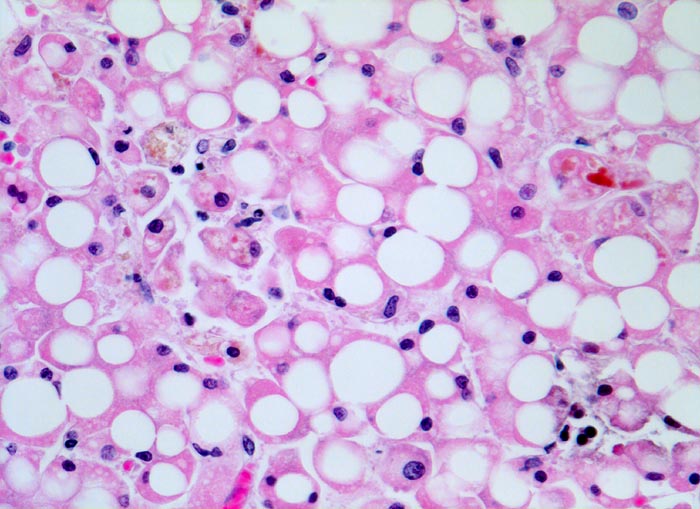

PathoPic – image database / PathoPic ID 4768 - grobtropfige Verfettung und hepatocanaliculäre Cholestase

grobtropfige Verfettung und hepatocanaliculäre Cholestase

Beschreibung

Die hepatocanaliculäre Cholestase ist völlig unspezifisch. Sie kann wie im vorliegenden Fall bei einer Sepsis oder beispielsweise als Arzneimittelnebenwirkung auftreten. Intrazytoplasmatische Galle ist manchmal kaum von Lipofuszin oder Hämosiderin unterscheidbar. Die in den Gallecanaliculi zwischen zwei Hepatozyten gelegene Galle ist jedoch aufgrund ihrer Lage einfach als Cholestase identifizierbar.

Histologie

320